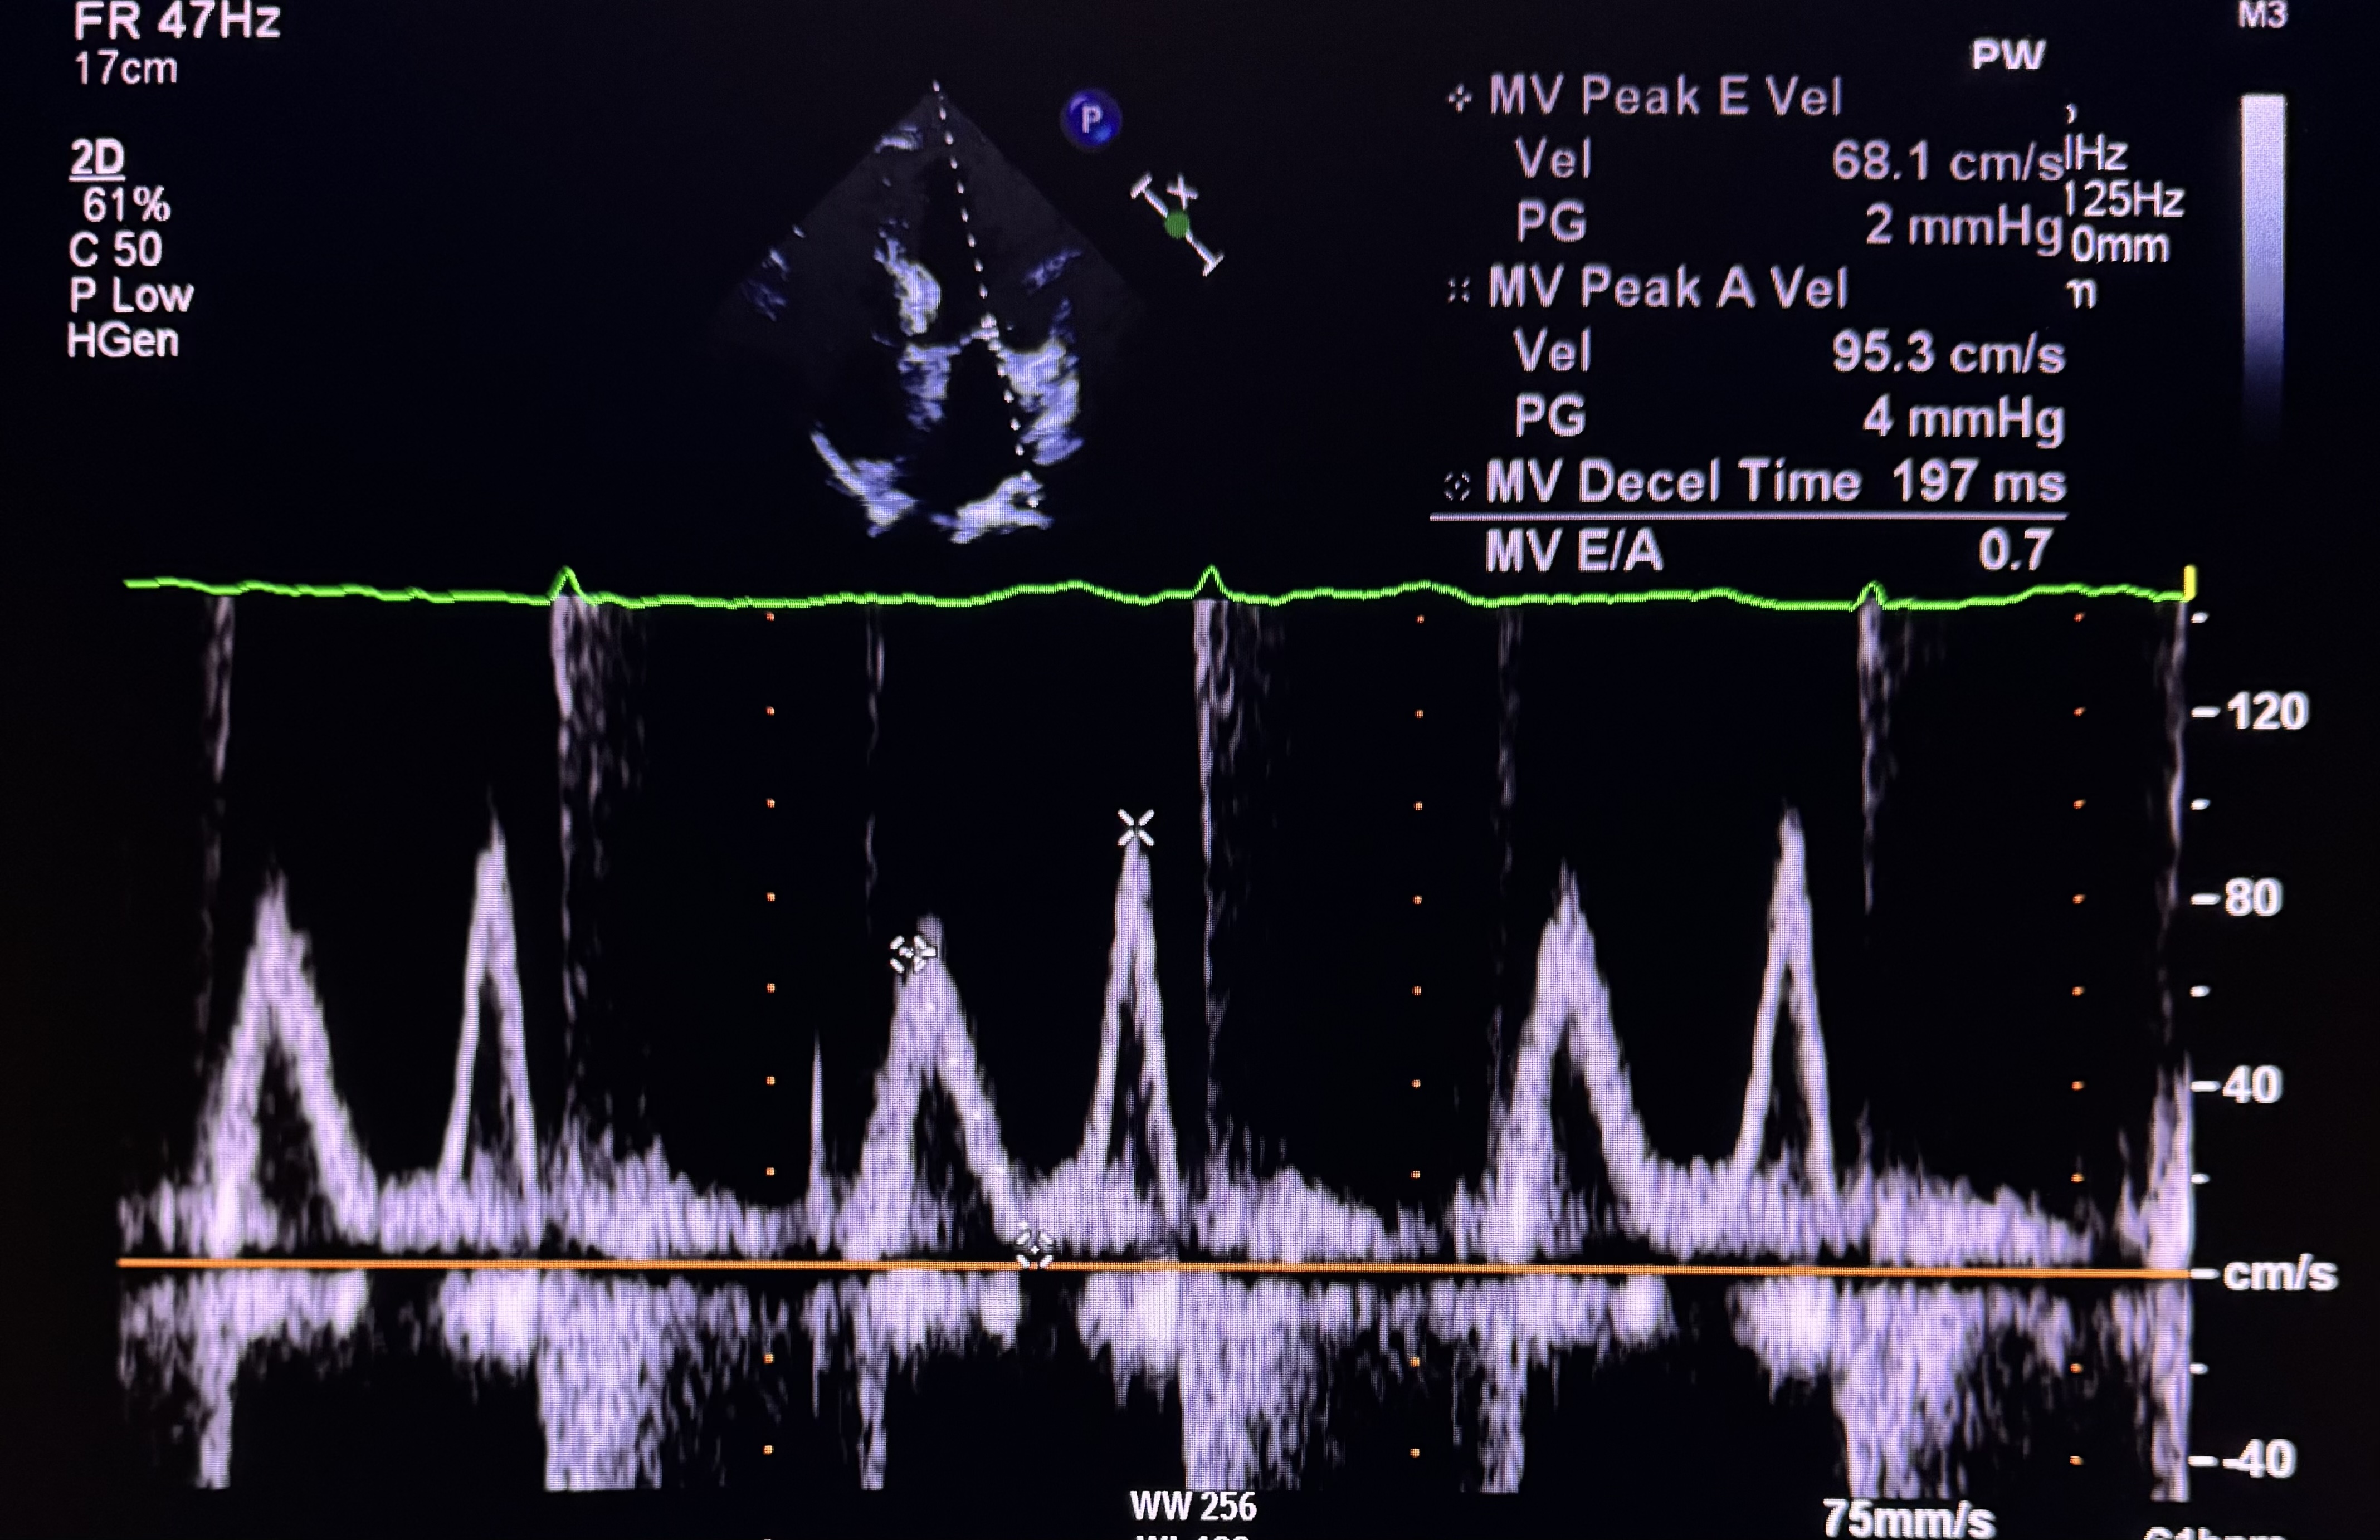

Relevant Test Results Prior to Catheterization

Cardiac Hs troponin was normal (20.4). Electrocardiogram demonstrated sinus rhythm 65 beats/min with isolated T inversion on lead IIIEchocardiogram demonstrated normal left ventricular systolic function with ejection fraction of 70%. Diastolic function corresponded with grade 1 dysfunction and no wall motion abnormalities. Her left ventricular size was normal with no evidence of mechanical complication of acute coronary syndrome. These informations led to the diagnosis of unstable angina